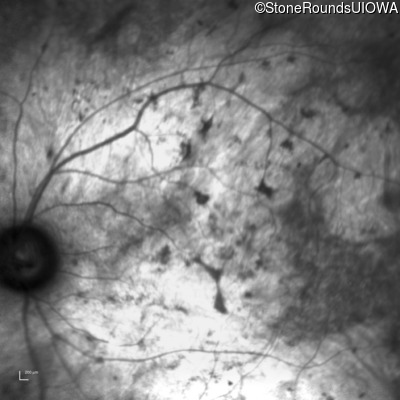

Infrared Fundus Photograph - Right - Light Perception

Exemplar

Infrared Fundus Photograph - Left - Light Perception